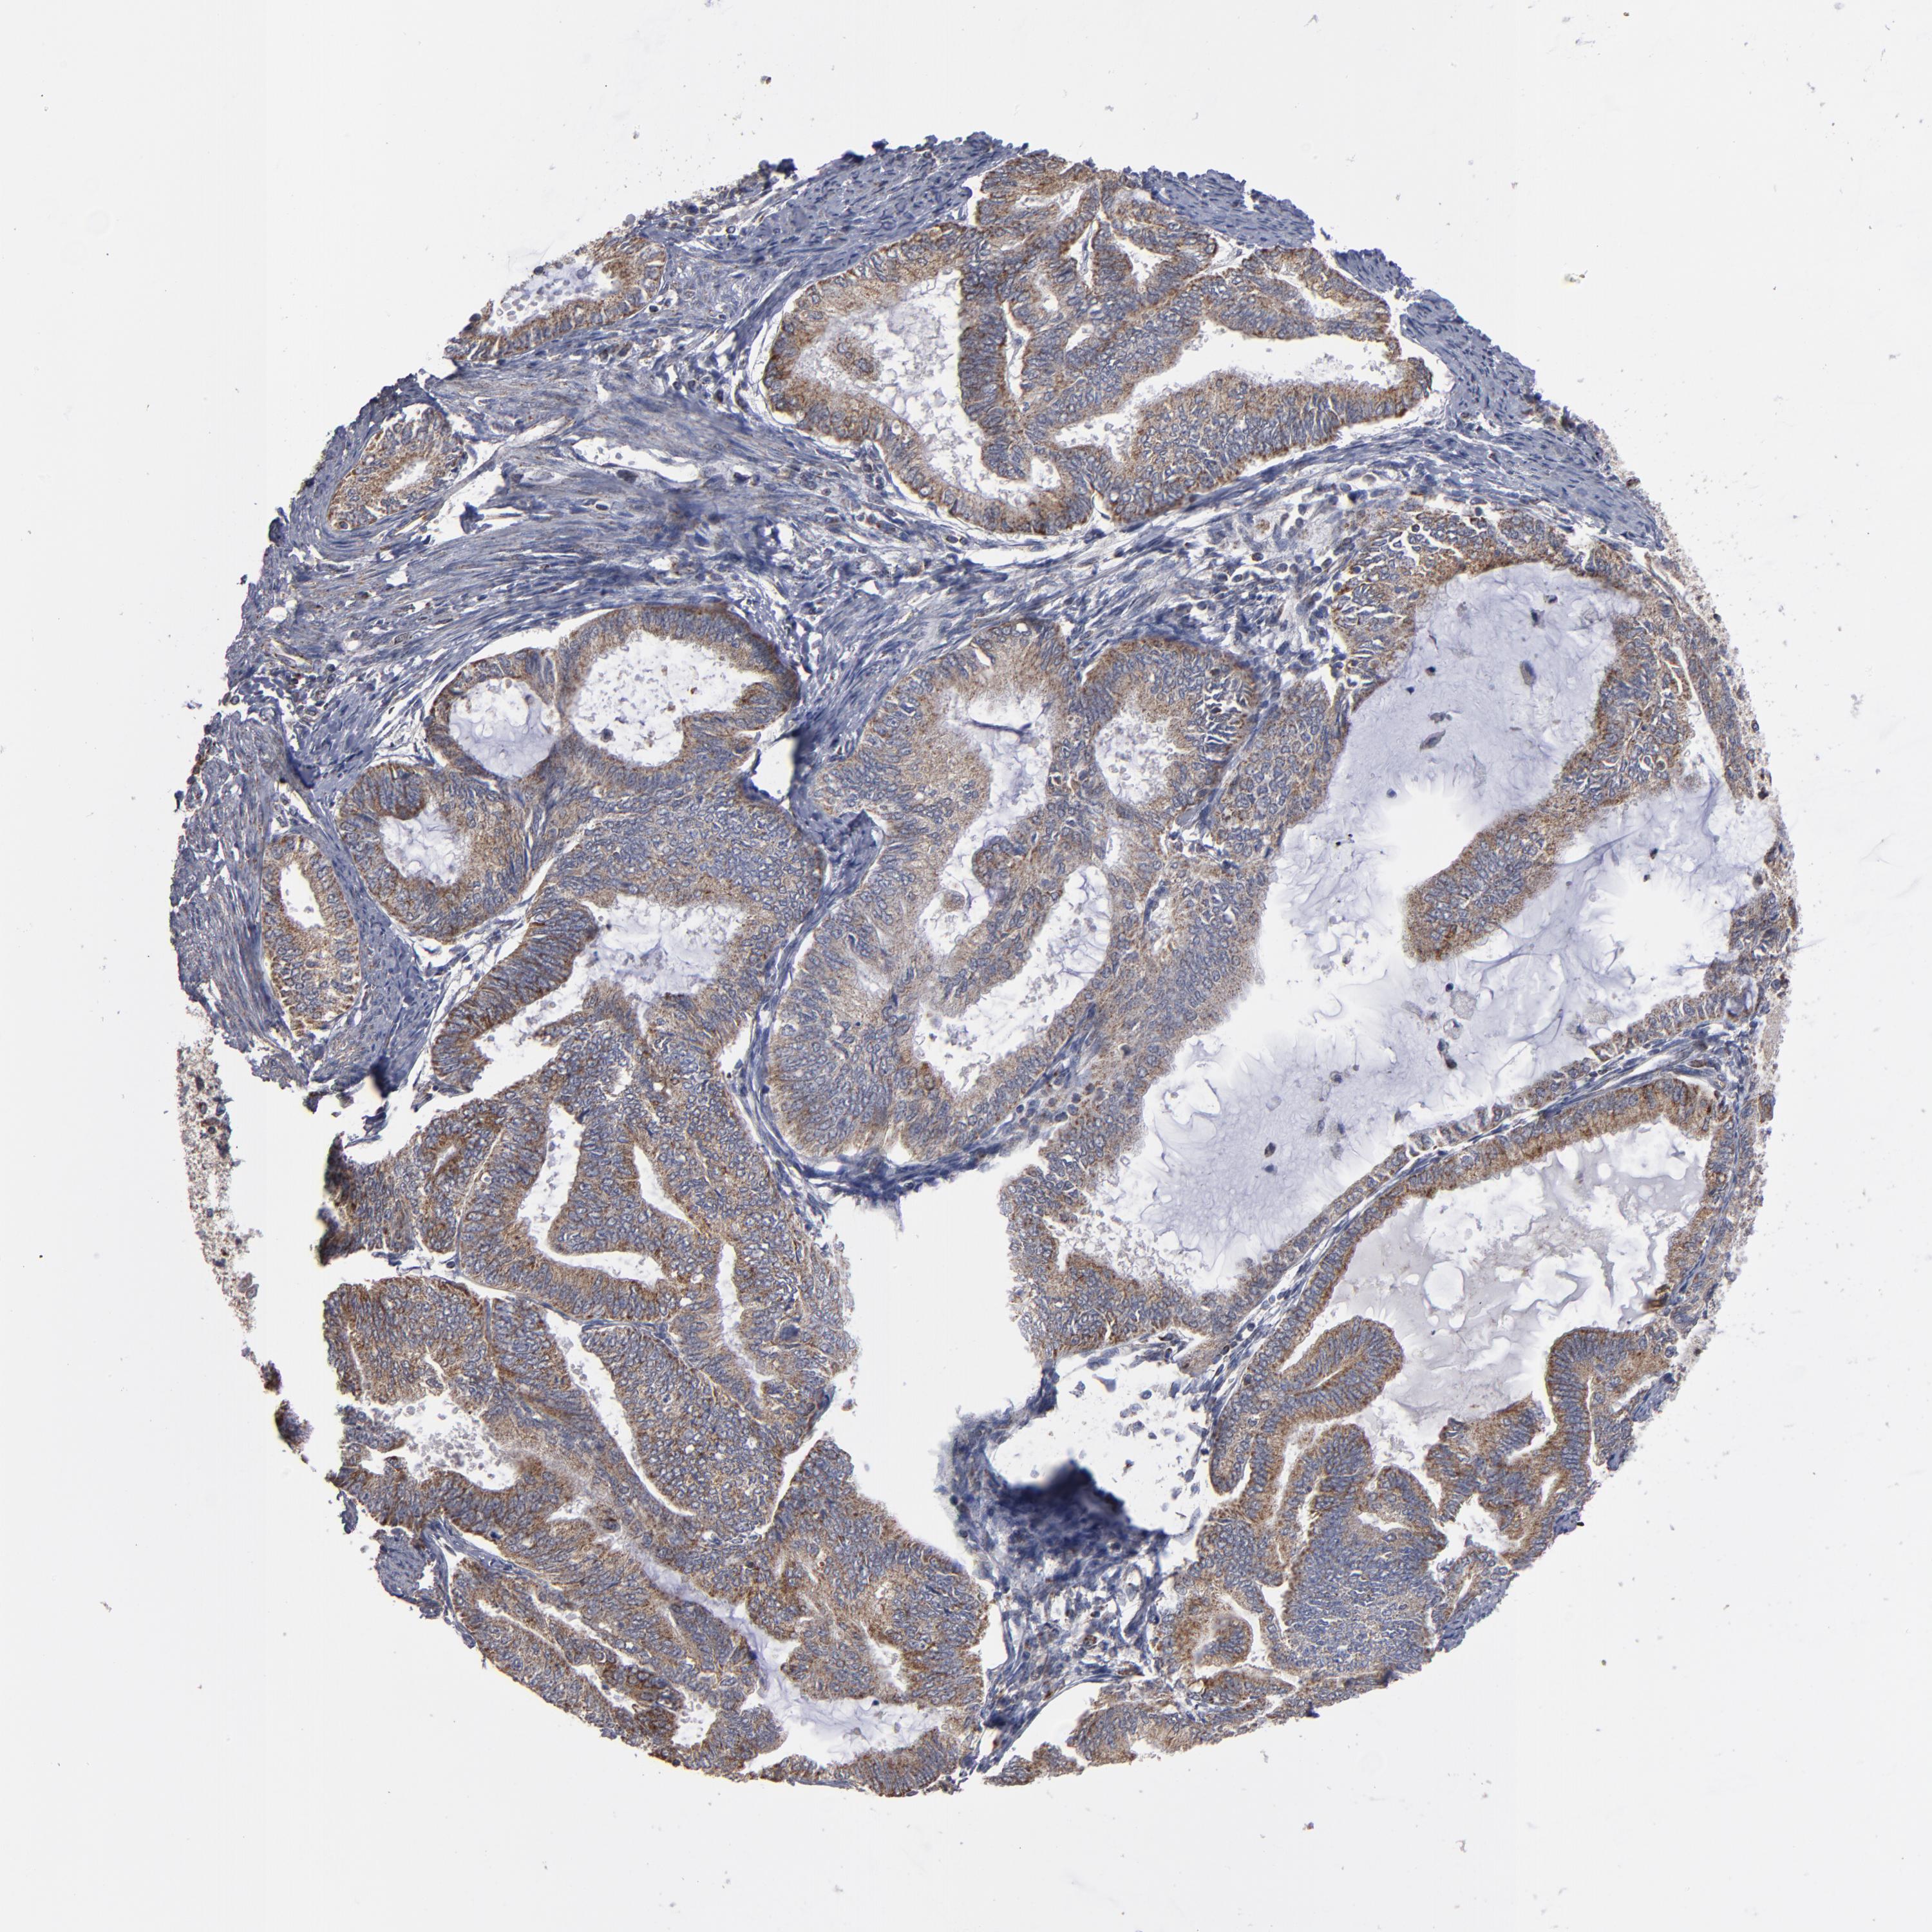

ENDOMETRIAL CANCER - Protein expressioni

A mouse-over function shows sample information and annotation data. Click on an image to view it in a full screen mode. Samples can be filtered based on level of antibody staining by selecting one or several of the following categories: high, medium, low and not detected. The assay and annotation is described here.

Note that samples used for immunohistochemistry by the Human Protein Atlas do not correspond to samples in the TCGA dataset.

Antibody stainingi

Antibody staining in the annotated cell types in the current human tissue is reported as not detected, low, medium, or high, based on conventional immunohistochemistry profiling in selected tissues. This score is based on the combination of the staining intensity and fraction of stained cells.

Each image is clickable and will lead to virtual microscopy that enables deeper exploration of all samples and also displays staining intensity scores, fraction scores and subcellular localization as well as patient and tissue information for each sample.

Antibody HPA002893

Staining

High

Medium

Low

Not detected

Intensity

Strong

Moderate

Weak

Negative

Quantity

>75%

75%-25%

<25%

None

Location

Nuclear

Cytoplasmic/membranous

Cytoplasmic/membranous,nuclear

Adenocarcinoma, NOS

Neoplasm, malignant, NOS